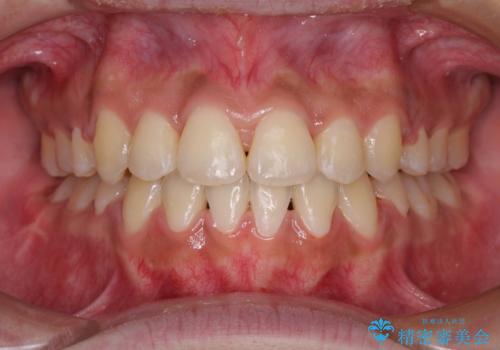

狭い上顎骨を拡大 著しい叢生を抜歯矯正で改善

- 上顎の著しい叢生と奥歯の咬みにくさを気にして来院された患者様です。

骨格的に上顎は狭く、下顎は右側にシフトしていたため、右側臼歯はクロスバイトとなっていました。

上顎骨を急速拡大装置により拡大し、ワイヤー装置による抜歯矯正治療を行うこととしました。